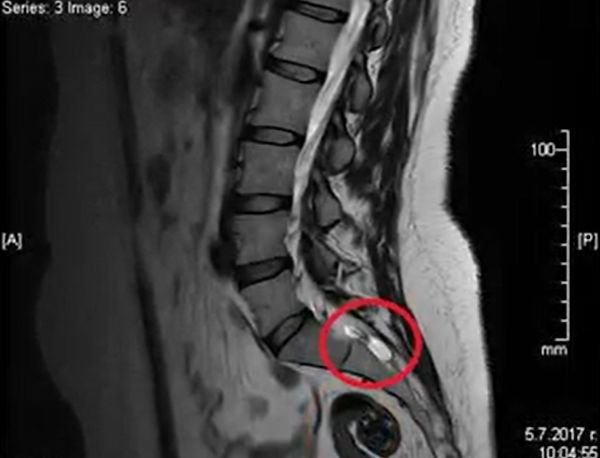

Научната програма стартира с встъпителна лекция на д-р Десислава Стойчева, специалист по образна диагностика. Д-р Стойчева има значителен опит в провеждането на образни изследвания при пациенти с кисти на Тарлов, като акцентът в нейната лекция ще бъде поставен върху възможностите на ядрено-магнитния резонанс на гръбначния стълб за диагностика на това рядко заболяване.